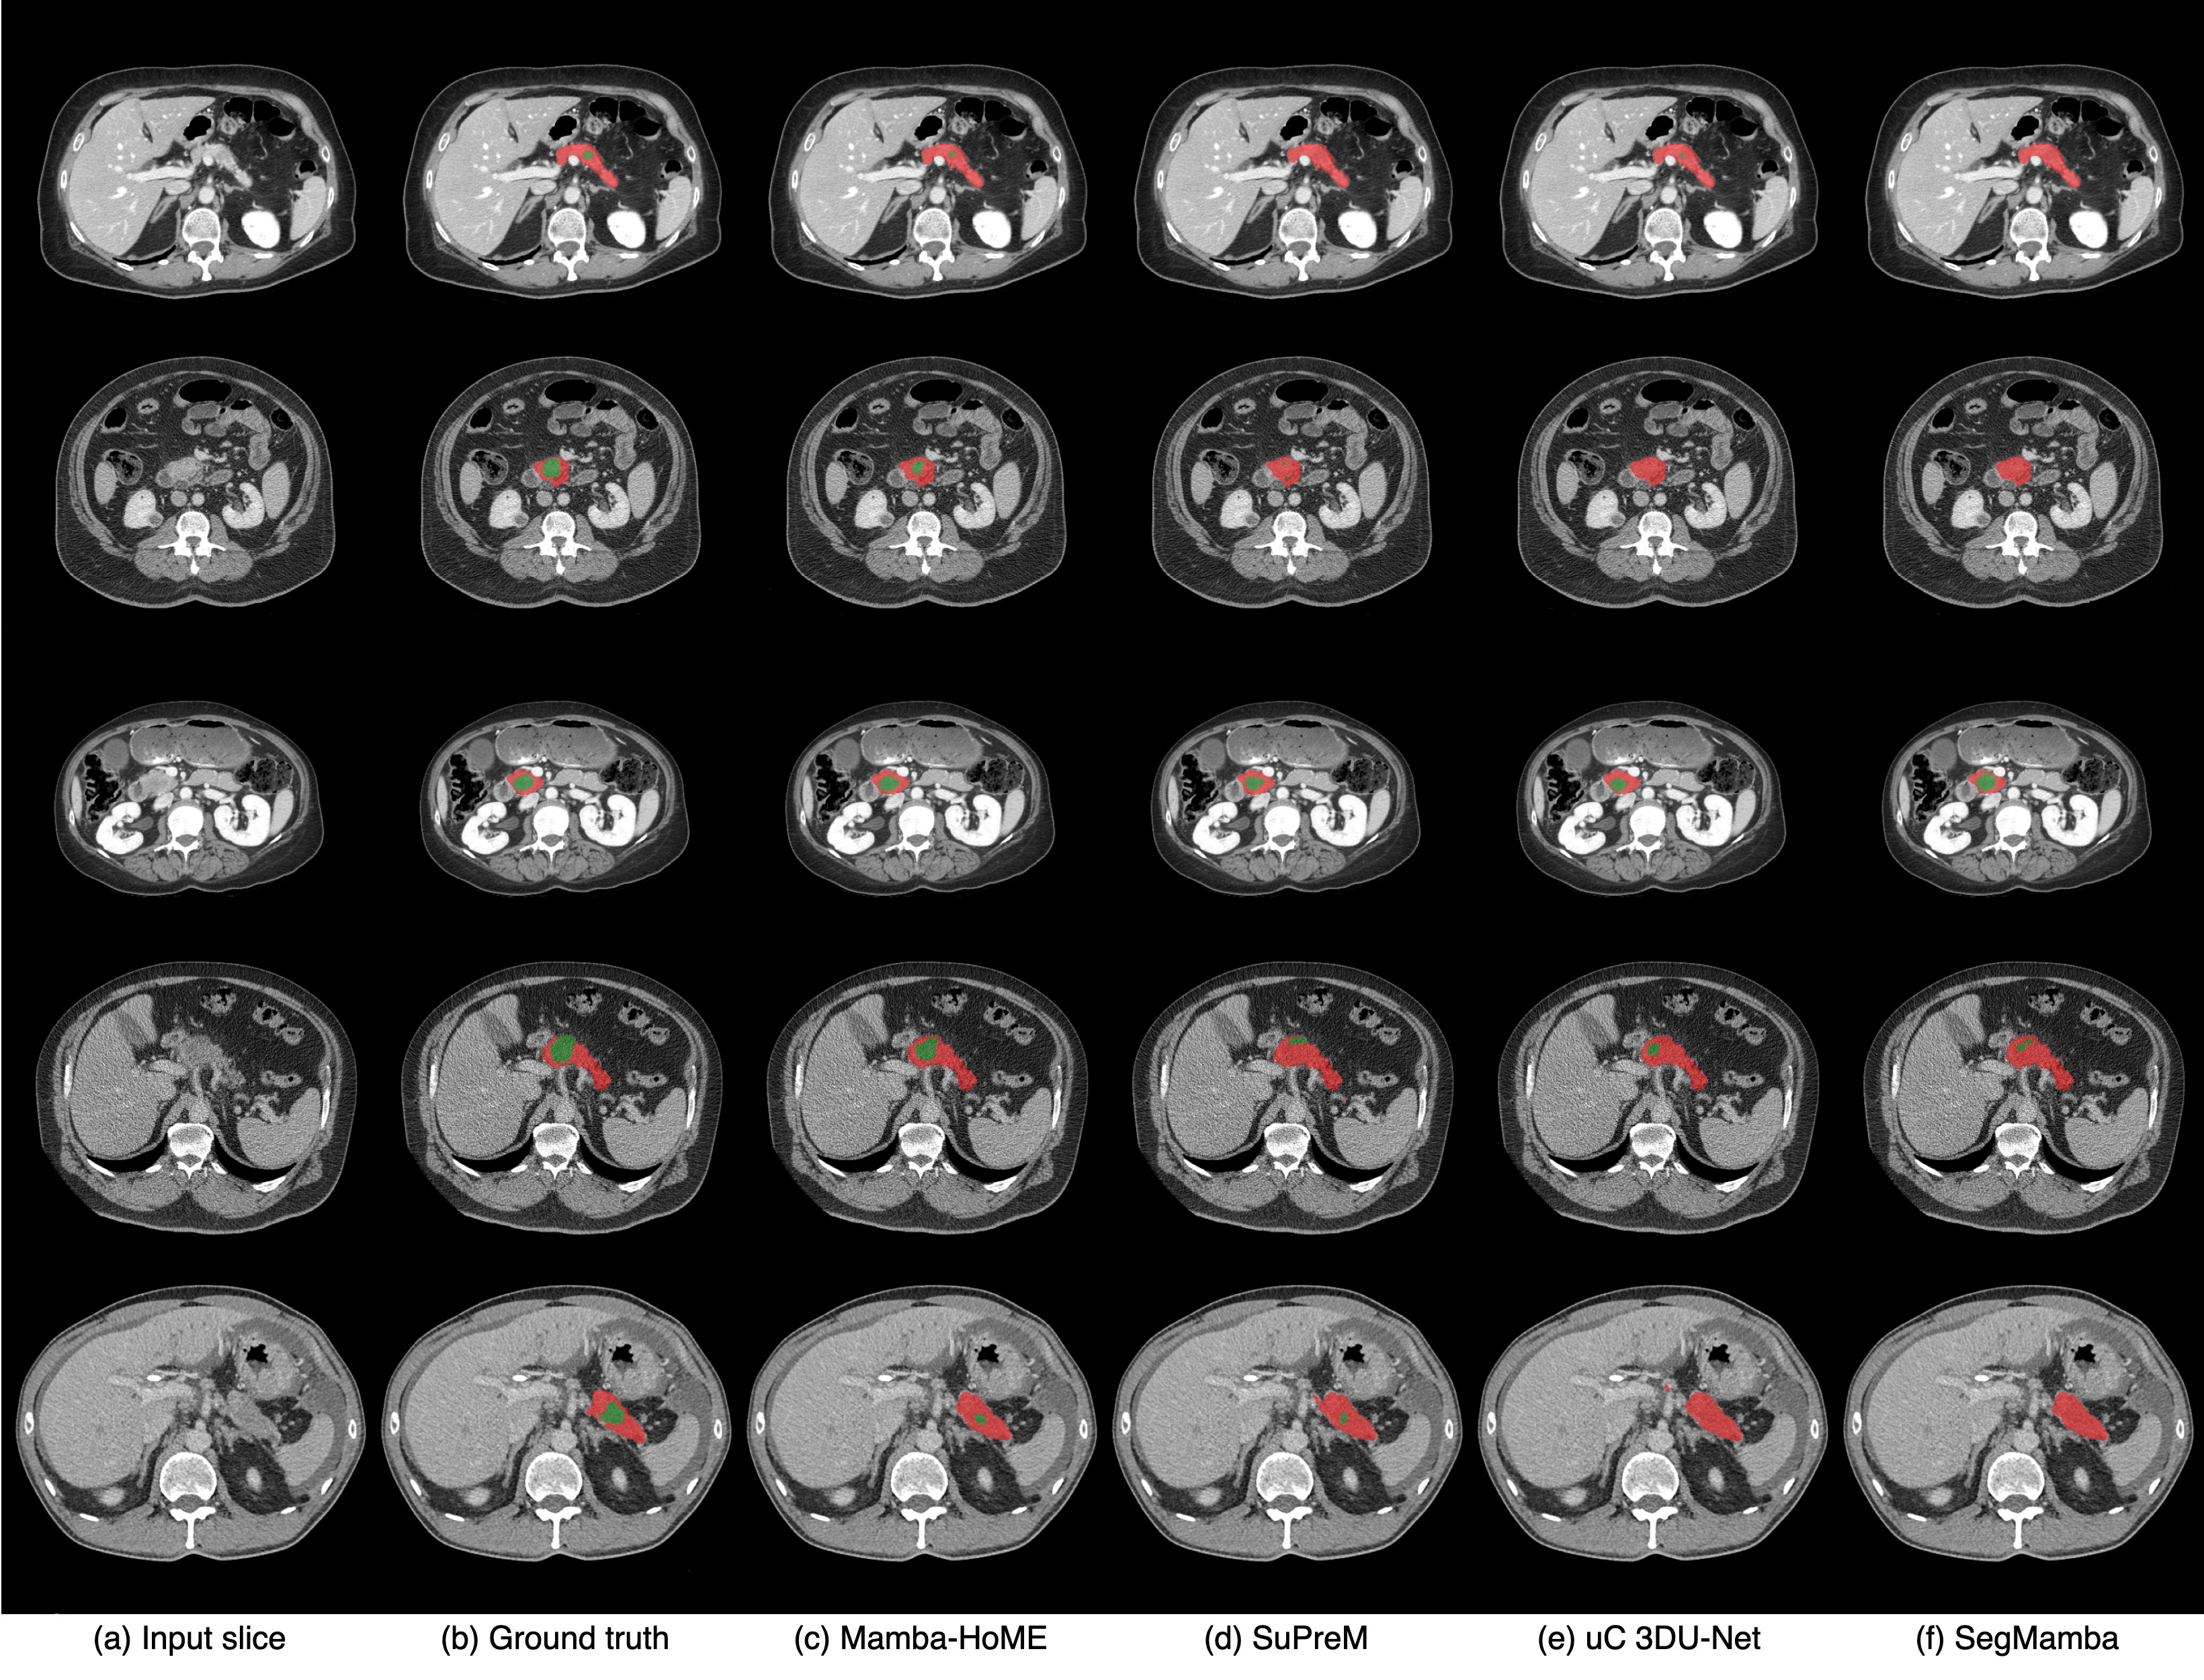

We compare our proposed Mamba-HoME with eight state-of-the-art approaches for 3D medical image segmentation, including uC 3DU-Net huang2025upping , Swin SMT plotka2024swin , VoCo-B wu2024voco , SuPreM li2024well , Hermes gao2024training , Swin UNETR tang2022self , VSmTrans liu2024vsmtrans , and SegMamba (baseline) xing2024segmamba , across four publicly available and one in-house dataset, covering diverse anatomical structures and imaging modalities, such as CT, MRI, and 3D US. Notably, both VoCo-B and SuPreM are pre-trained on large-scale CT scans using self-supervised and supervised learning approaches, respectively. Additionally, we evaluate Mamba-HoME trained from scratch against Mamba-HoME pre-trained with a supervised learning approach to assess the impact of pre-training on segmentation performance. Detailed quantitative and more qualitative results for benchmarking datasets can be found in Appendix C, and Appendix E, respectively.

Quantitative results. Results for our proposed method, Mamba-HoME, on the PANORAMA and in-house datasets are shown in Table 1. Results for other modalities, including AMOS (CT/MRI), FeTA 2022 (fetal MRI), and MVSeg (3D US), are presented in Table 2, Table 3, and Table 4, respectively.

Our proposed method, Mamba-HoME, demonstrates consistent performance improvements over state-of-the-art baselines across all benchmark datasets and three imaging modalities. Evaluated under two distinct configurations (scratch and pre-trained), Mamba-HoME achieves superior segmentation accuracy, obtaining the best results in terms of both DSC and HD95. Despite having a relatively large number of parameters (170.1M) compared to competing methods, it exhibits low GPU memory usage during inference (see Table 1), a crucial advantage for processing high-resolution 3D medical data. Although inference is approximately 30% slower than the baseline, the performance gains present a compelling trade-off between accuracy and efficiency. The Wilcoxon signed-rank test indicates a significant difference between Mamba-HoME and other state-of-the-art methods, with a significance threshold of p<0.05p<0.05.

To evaluate generalizability, we compare the proposed Mamba-HoME with several state-of-the-art networks. Specifically, we investigate four configurations on the AMOS dataset: (1) training solely on CT, (2) pre-training all models on CT and fine-tuning on MRI, (3) training solely on MRI, and (4) joint training on both CT and MRI. Table 2 shows that Mamba-HoME demonstrates superior generalizability across modalities compared to other models. Trained from scratch and further pre-trained on large-scale CT and MRI datasets, Mamba-HoME exhibits strong cross-modal generalizability to 3D ultrasound data, a modality with distinct challenges such as high noise and lower resolution. Leveraging robust, modality-agnostic feature representations, the pre-trained model adapts to 3D ultrasound via efficient fine-tuning, outperforming state-of-the-art methods in both DSC and boundary HD95 metrics, as shown in Table 4. Qualitative results in Figure 2 further illustrate its ability to handle ultrasound-specific artifacts. This cross-modal transferability highlights the model’s versatility across diverse imaging modalities. Moreover, Mamba-HoME demonstrates strong generalizability to external datasets within the same modality, especially MSD Pancreas and in-house CT dataset for PDAC and pancreas segmentation, outperforming several state-of-the-art methods in both DSC and HD95 metrics (see Table 11). Detailed results for the generalizability analysis can be found in Appendix F.